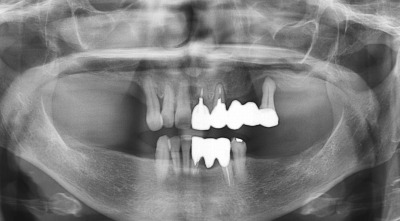

インプラント症例1 奥歯がほとんどない女性の方

嘔吐反射が強く、ノドに物が触れると気持ち悪いので、入れ歯は入れれないという理由でインプラント希望です。

噛む所が無いので、とにかく早く噛める様にしてあげたいところです。

先月左の上はすでにインプラントを2本入れまして、今日は右上に2本のインプラントを入れました。

鼻腔が近くて当初1本の予定でしたが、歯肉側に少し骨を造って (GBR) 2本にしました。ギリギリでした。

期間をかけて、鼻腔に骨を造る場合(サイナスリフト)もありますが、今回は早く噛めるようにまずはできる所からしました。

多少でも骨が残ってまいすからよかったです。下の奥歯は5月と6月にインプラントを入れる予定です。